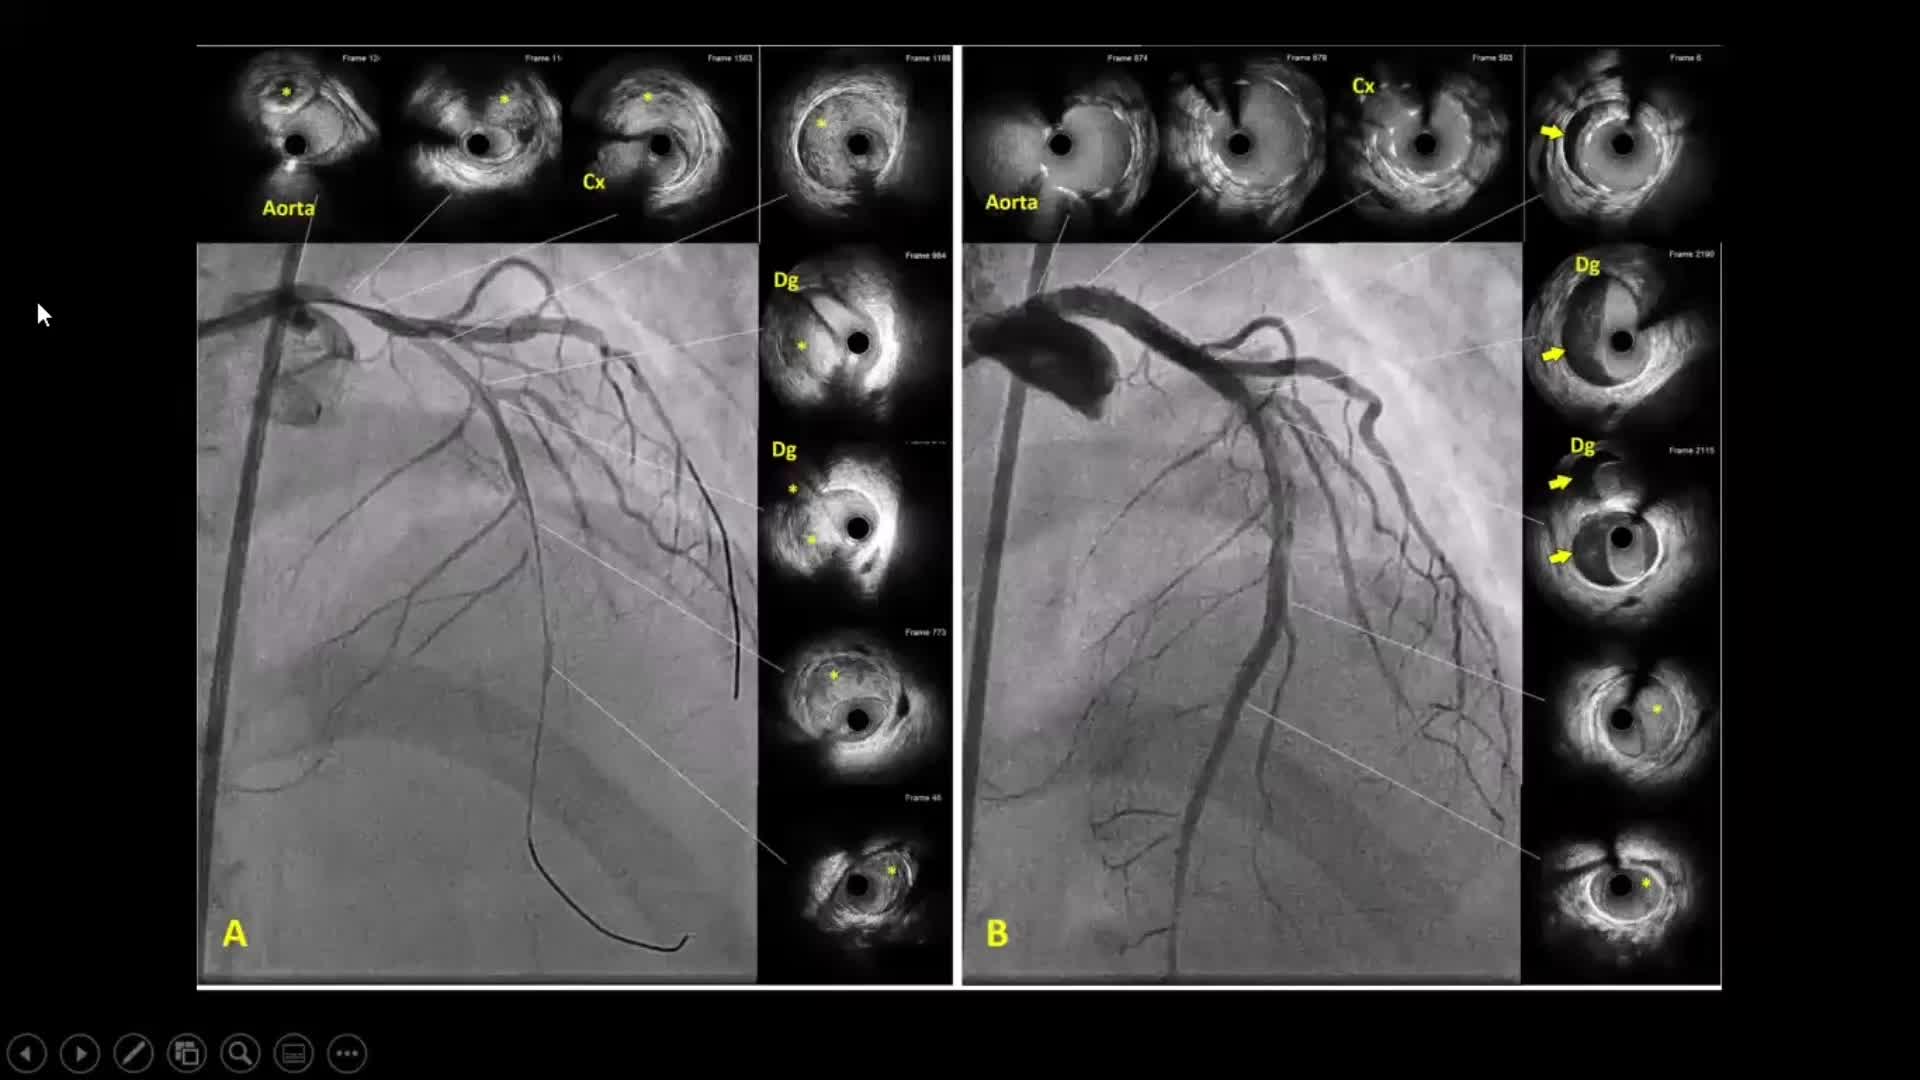

How to perform good co-registration measurements using iFR and IVUS - Prof Carlo Di Mario

Using SyncVision Co-registration to distinguish between focal and diffuse coronary disease. - Prof Giuseppe Tarantini

Best practices and personalised medicine in complex PCI - Prof Javier Escaned

Essential steps for physiology-based PCI planning and guidance - Dr Allen Jeremias

Coronary Bifurcations: An Update on Diagnosis, PCI planning and Imaging and PhysiologyGuidance - Dr Dejan Milasinovic